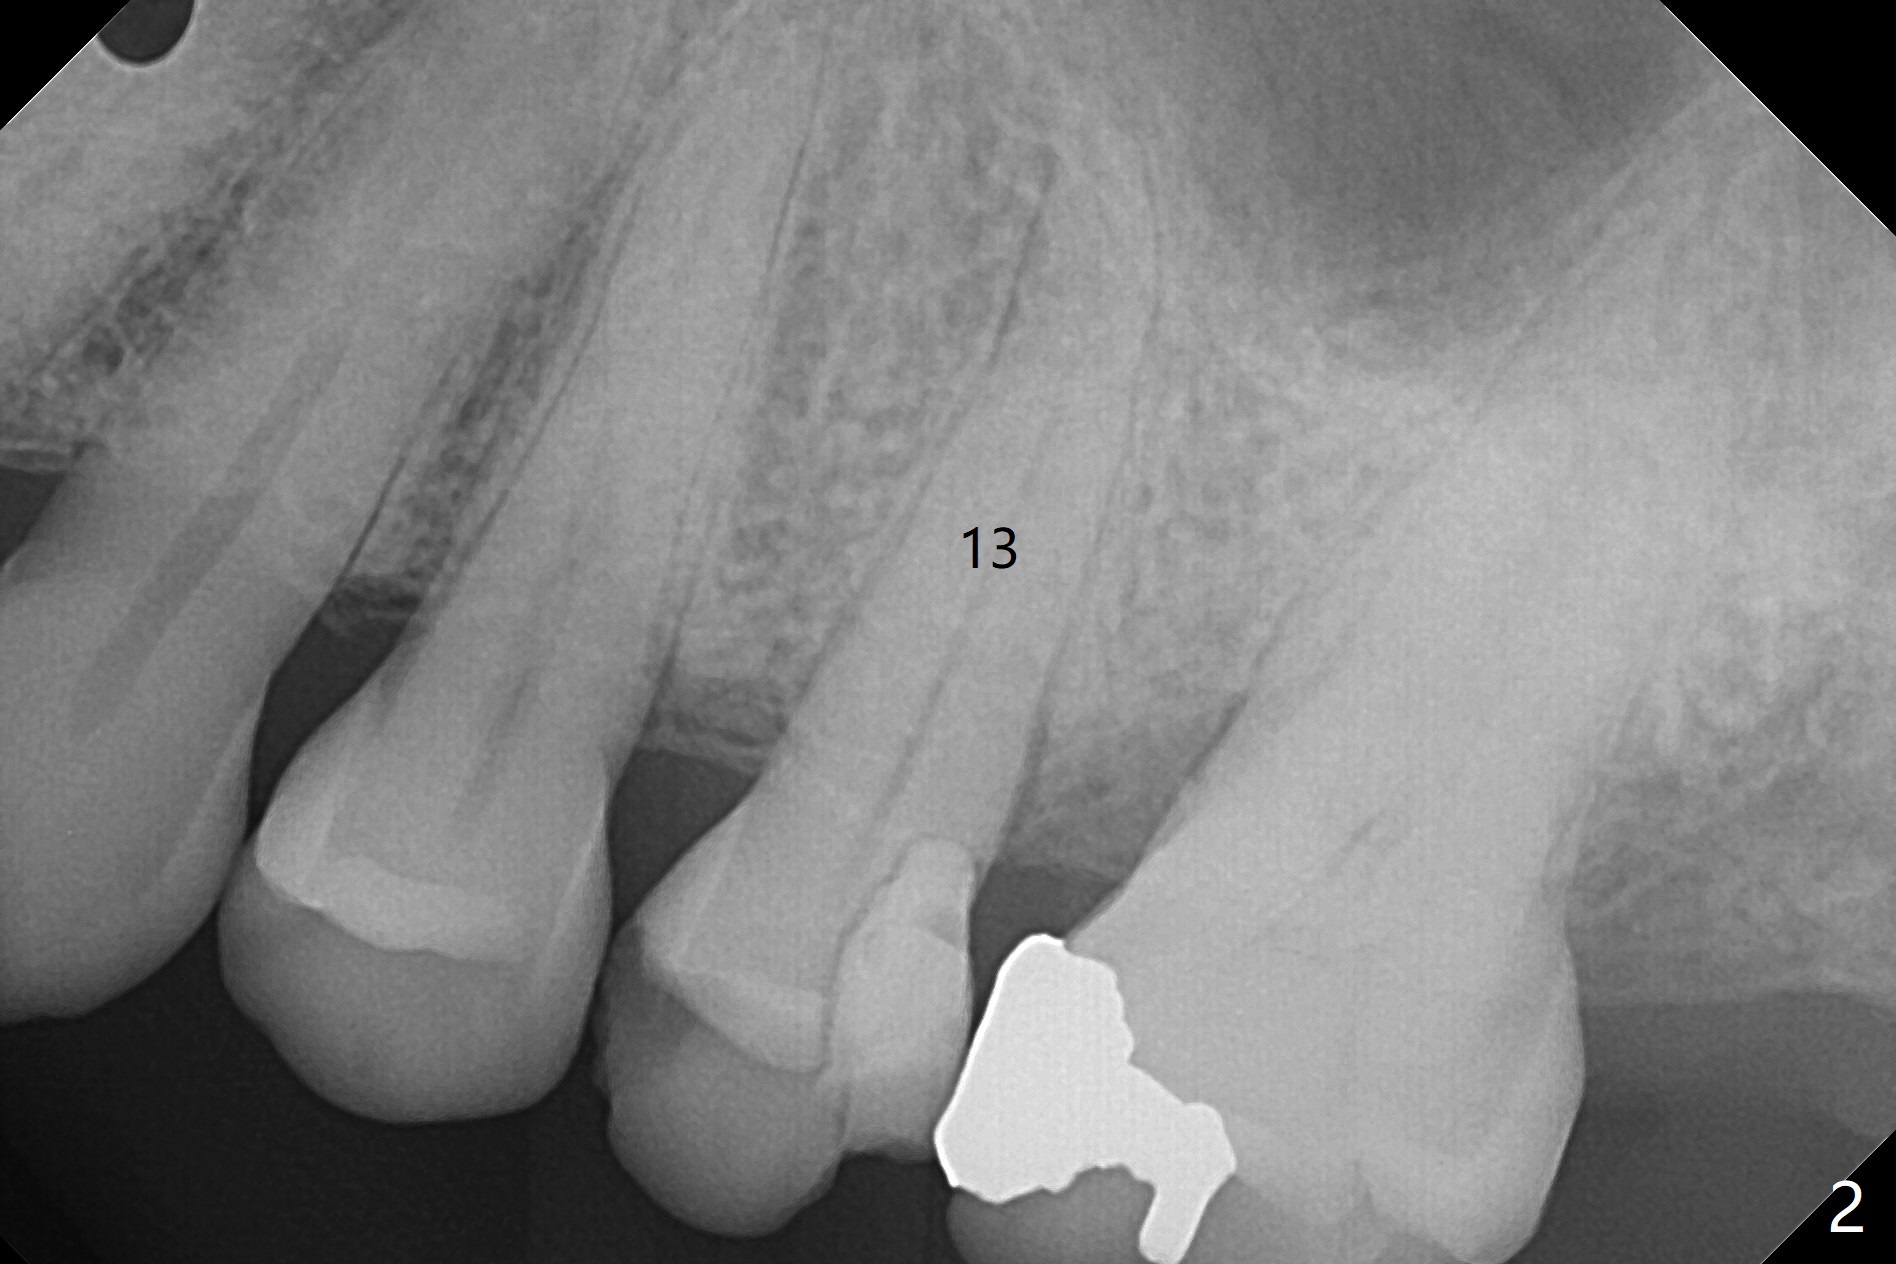

A 65-year-old woman cracks the tooth #13 (Fig.2) while the implants placed at #2 and 3 in her home country are osteointegrating (Fig.1). Extraction turns out to be surgical; after removing the curved root, the socket is large. Osteogen plug is placed for socket preservation due to finance (Fig.3 *). While the socket has healed, the buccal plate has collapsed 2 months postop (Fig.4).